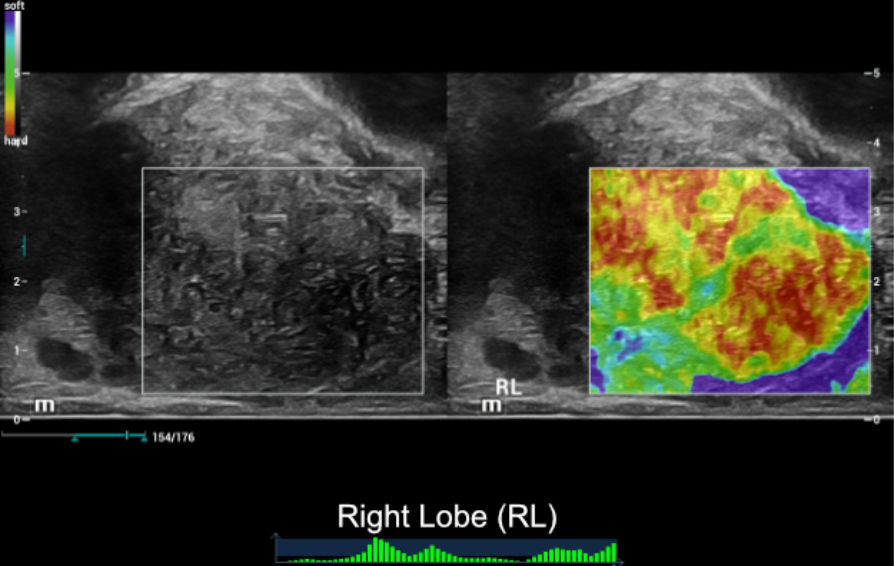

??? ??? ????? ?? ?? ??-?? ??? ???? ???? ???????. ????? ?? ??? ?? ?? 2?? ??? ???? ???, ???? ???? ?????, ???? ????? ????? ??? ?? ? ?????. ???? ???????(NTE: Natural Touch Elastography)? 2D ?? ?? ???(STE: Sound Touch Elastography)? ??? ??????? ??? ?? ??? ????? ?? ???????.

NTE ŌĆō ???? ???????:

??? ?? ???(SWE)? ??? 34kPa, ??? 115kPa? ?? ??(??6). ?? ??? SWE? ???? ? ???? ? ??.(?? = 19 kPa, ?? = 36 kPa). (??7) ????? ??? ????(PZ)?? ???? ?? ???? ???. ????(TZ)? ??? ???? ?? ????(PZ)?? ? ???. ????(TZ)? ????(PZ)? ??? ???.

- NTE? ??? 2D ????? ??? ??? ??? ?? ??? ??? ???????. ??? ???? ?????? ?? ????? ?? ??? ??? ??? ???? ?? ??? ???????.